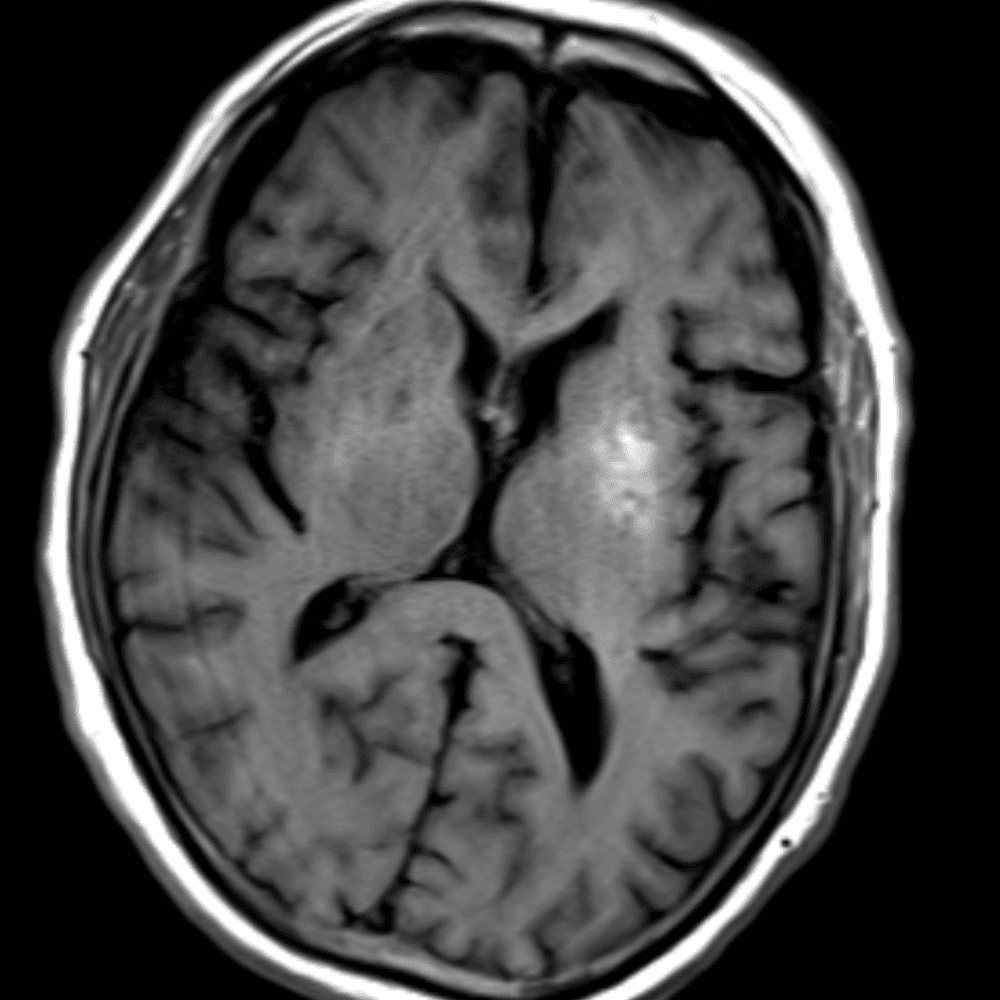

์—ฐ์Šต

๋ฏธ๋ฌ˜ํ•˜๊ฑฐ๋‚˜ ์–ด๋ ค์šด ์‚ฌ๋ก€์™€ ์ผ๋ถ€ ์ •์ƒ ์‚ฌ๋ก€๋ฅผ ํฌํ•จํ•˜์—ฌ ๋‹น์ง์„ ์‹œ๋ฎฌ๋ ˆ์ด์…˜ํ•ฉ๋‹ˆ๋‹ค.

50 ์‚ฌ๋ก€